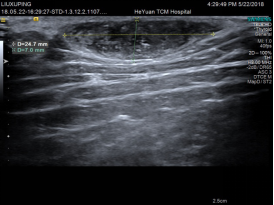

↑肱二头肌长头肌腱断裂